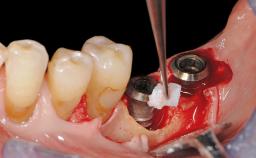

In this case, Mario Roccuzzo utilizes surgical bone regeneration treatment around implant 46 using a bone graft substitute and a connective tissue graft to resolve peri-implant inflammation, reduce the probing depths, and prevent further progression of disease.

A 58-year-old-male patient was referred in February 2007 for implant placement in the right mandibular molar area. Two tissue level implants were inserted at sites 44 and 46, respectively, to support a three-unit fixed dental prosthesis (FDP).